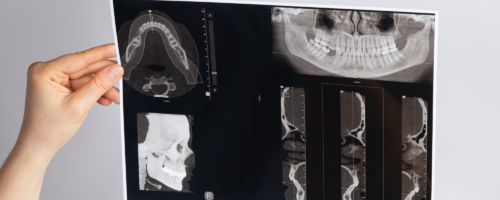

In der Beta Klinik Bonn bieten wir innovative diagnostische Verfahren und modernste Behandlungsmethoden der Fehlbiss-Chirurgie an, um unseren Patientinnen und Patienten zu einem besseren Lebensgefühl zu verhelfen. Erfahren Sie bei uns alles Wichtige zu Zahn- und Kieferfehlstellungen – welche es gibt, Symptome, Ursachen und Behandlungsmöglichkeiten.